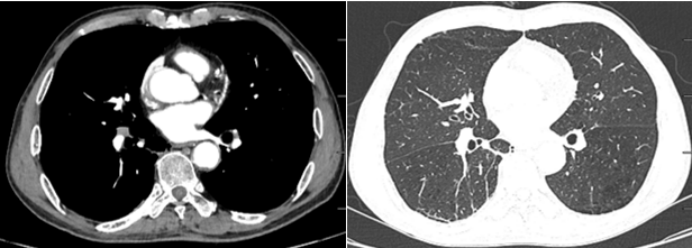

2024年2月18日,患者于外院体检,胸部CT示:右肺下叶内基底段肿块影(3.4 cm×3.0 cm)(图1)2024年2月29日,我院CT引导下经皮肺穿刺,病理证实为鳞状细胞癌。2024年3月11日,PET-CT示:右肺下叶鳞状细胞癌伴肺门纵隔内淋巴结转移(cT4N2M0ⅢB)。2024年3月16日予TP(紫杉醇+顺铂)+替雷利珠单抗治疗3个周期。7月9日复查胸部CT,可见原有肿块明显好转(图2)

图片

1  患者外院胸部CT(2024-02-18)

2   复查胸部CT(2024-07-09)